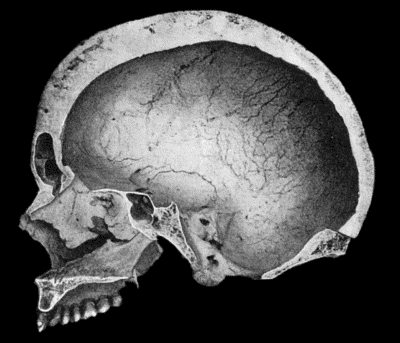

| 134. | Changes in the Skull resulting from Ostitis Deformans | 474 |